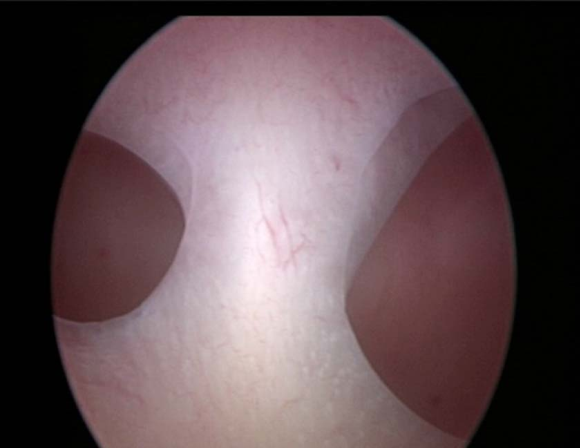

不完全纵隔子宫宫腔镜下表现

一般无症状。临床上主要表现为影响生育期妇女的妊娠结局,包括反复流产、早产、胎膜早破等表现,其中以反复流产为最常见。经阴道超声检查是目前最常用的诊断方法,表现为两个内膜回声区域,子宫底部无明显凹陷切迹。子宫输卵管碘油造影(HSG)有助于了解宫腔形态,评估双侧输卵管通畅与否。宫腹腔镜联合检查是诊断纵隔子宫的“金标准”方法。

纵隔子宮影响生育时,应予手术治疗。可在腹腔镜监视下通过宫腔镜切除纵隔,通常于手术后3个月即可妊娠,妊娠结局良好。